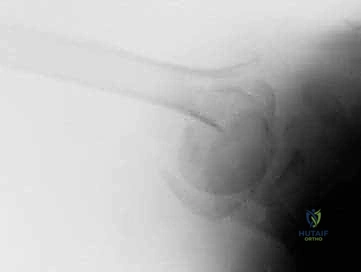

Proximal humerus fractures involve isolated or combined injuries to the greater tuberosity, lesser tuberosity, articular segment, and proximal humeral shaft. Overall, proximal humerus fractures account for 4% to 5% of all fractures.2,8,11,13 ## ANATOMY The proximal humerus consists of four segments: the greater tuberosity, lesser tuberosity, articular segment, and humeral shaft (FIG 1). The most cephalad surface of the articular segment is, on average, 8 mm above the greater tuberosity.18 Humeral version averages 29.8 degrees (range, 10 to 55 degrees).18,23 The intertubercular groove lies between the tuberosities and forms the passageway for the long head of the biceps as it traverses from the intra-articular origin into the distal arm. The tuberosities attach to the articular segment at the anatomic neck. The greater tuberosity has three facets for the corresponding insertions of the supraspinatus, infraspinatus, and teres minor tendons; the lesser tuberosity has a single facet for the subscapularis. The deltoid, pectoralis major, and latissimus dorsi all insert on the humerus distal to the surgical neck. These soft tissue attachments contribute to the deforming forces sustained with proximal humerus fractures. Illustration 1 for Hemiarthroplasty for Proximal: Effective Treatment for Fractures --- Illustration 2 for Hemiarthroplasty for Proximal: Effective Treatment for Fractures ### FIG 1 • Neer classification of proximal humerus fractures: 1, greater tuberosity; 2, lesser tuberosity; 3, articular surface; 4, shaft. The humeral head receives its blood supply from the antero-lateral branch of the anterior humeral circumflex artery (the arcuate artery of Laing) and the posterior humeral circumflex artery. The artery of Laing courses parallel to the lateral aspect of the long head of the biceps and enters the humeral head at the interface between the intertubercular groove and the greater tuberosity.20 More recent studies have indicated that the posterior branch may play a larger role in perfusion of the fractured humeral head, reducing the risk of osteonecrosis.10,15,16 ## PATHOGENESIS The incidence of proximal humerus fractures is increasing with an aging population and associated osteoporosis. The mechanism of injury may be indirect or direct and secondary to high-energy collisions in younger patients (eg, motor vehicle accidents, athletic injuries) or falls from standing height in elderly patients. Pathologic fractures from primary or metastatic disease should be included in the differential diagnosis. Risk factors for the development of proximal humerus fractures in the elderly patient population include low bone density, lack of hormone replacement therapy, previous fracture history, three or more chronic illnesses, and smoking.17 ## NATURAL HISTORY Neer's classic study in 1970 compared the results of nonoperative treatment with hemiarthroplasty for three-and fourpart displaced proximal humerus fractures. No satisfactory results were found in the nonoperative group owing to inadequate reduction, nonunion, malunion, and humeral head osteonecrosis with collapse.22 Stableforth28 reaffirmed this in a study in which patients were randomized to nonoperative management or prosthetic replacement. The patients with displaced fractures treated nonoperatively had worse overall results for pain, range of motion, and activities of daily living. Olerud et al25 most recently demonstrated significantly improved quality of life with a trend toward pain scores with four-part fractures treated with hemiarthroplasty versus observation. ## PATIENT HISTORY AND PHYSICAL FINDINGS A thorough history and complete physical examination should be performed. History should include mechanism of injury, premorbid level of function, occupation, hand dominance, history of malignancy, and ability to participate in a structured rehabilitation program.14 Illustration 3 for Hemiarthroplasty for Proximal: Effective Treatment for Fractures --- Illustration 4 for Hemiarthroplasty for Proximal: Effective Treatment for Fractures ### FIG 2 • A. Anteroposterior (AP) and (B) scapular “Y” views of a displaced four-part proximal humerus fracture without evidence of concomitant dislocation. (Copyright Kamal I. Bohsali, MD.) A review of systems should involve queries regarding loss of consciousness, paresthesias, and ipsilateral elbow or wrist pain. On physical examination, the orthopaedic surgeon should look for swelling, soft tissue injuries, ecchymosis, and deformity. Posterior fracture-dislocations will demonstrate flattening of the anterior aspect of the shoulder with an associated posterior prominence. Anterior fracture-dislocations present with opposite findings.14 ## IMAGING AND OTHER DIAGNOSTIC STUDIES Appropriate radiographs include biplanar views of the shoulder14 (FIG 2). If the axillary view cannot be obtained because of patient discomfort, alternate views such as the Velpeau trauma axillary view can be used to evaluate and classify the glenohumeral articulation.2 The Neer classification is based on the four anatomic segments of the proximal humerus: the humeral head, the greater and lesser tuberosities, and the humeral shaft (see FIG 1).11 Number of parts is based on 45 degrees of angulation or 1 cm of displacement from neighboring segments. The AO/ASIF/OTA Comprehensive Long Bone Classification system distinguishes the valgus impacted fourpart proximal humerus fracture from other four-part fractures with partial preservation of the vascular inflow to the articular segment through an intact medial capsule.8,19,26 The current fracture classification systems have fair interobserver reliability, even with the addition of computed tomography (CT) scans. Despite the limitations of these systems, they remain clinically useful when deciding on nonoperative versus operative treatment.2,11 CT scans may be helpful in evaluating tuberosity displacement and articular surface involvement.12,14 ## DIFFERENTIAL DIAGNOSIS Acute hemorrhagic bursitis Traumatic rotator cuff tear Simple dislocation Acromioclavicular separation Calcific tendinitis2 ## NONOPERATIVE MANAGEMENT Nonoperative treatment usually is reserved for minimally displaced fractures of the proximal humerus, which account for nearly 80% of these injuries. The characteristics of the fracture (ie, bone quality, fracture orientation, concurrent soft tissue injuries), the personality of the patient (eg, compliant, realistic expectations, mental status), and surgeon experience all affect the decision to proceed with operative intervention. Moribund individuals and patients unable to cooperate with a postoperative rehabilitation program (eg, closed head injury) are not appropriate candidates for operative intervention. In general, nonoperative management of complex, displaced proximal humerus fractures has not proven as successful. Initial immobilization with a sling and axillary pad may be helpful. Gentle range-of-motion exercises may be started by 7 to 10 days after the fracture event when pain has decreased and the patient is less apprehensive.2 Intermittent biplanar radiographs are essential to determine additional displacement and the interval stage of healing.2 Active and active-assisted range-of-motion exercises are initiated with evidence of radiographic union. Inform the patient that he or she may never attain symmetric range of motion or strength when comparing the affected versus the uninjured side. ## SURGICAL MANAGEMENT The goal of surgery is to anatomically reconstruct the glenohumeral joint with restoration of humeral height, replication of appropriate prosthetic retroversion, and establishment of secure tuberosity fixation. Prosthetic replacement is the preferred treatment of most four-part fractures, three-part fractures and dislocations in elderly patients with osteoporotic bone, head-splitting articular segment fractures, and chronic anterior or posterior humeral head dislocations with more than 40% of the articular surface involvement.1,2,23 Several studies have indicated that the outcome of primary hemiarthroplasty for acute proximal humerus fractures is superior to that from late reconstruction.6,24 There are commercially available fracture-specific stems that allow for improved bone grafting and tuberosity placement, some with bone windows with reduced proximal stem diameter and others with a suture collar with potential conversion to a reverse shoulder prosthesis (FIG 3A,B). ## Preoperative Planning Although some studies have suggested urgent intervention (ie, within <48 hours), most authors recommend preoperative planning with a careful neurovascular assessment of the injured shoulder, medical optimization of the patient, and preoperative templating with standard radiographs of the contralateral uninjured shoulder.12 A CT scan may provide improved characterization of the fracture pattern such as intra-articular involvement and degree of tuberosity comminution for surgical planning.2 An interscalene block (regional anesthesia) may be used to supplement general anesthesia.